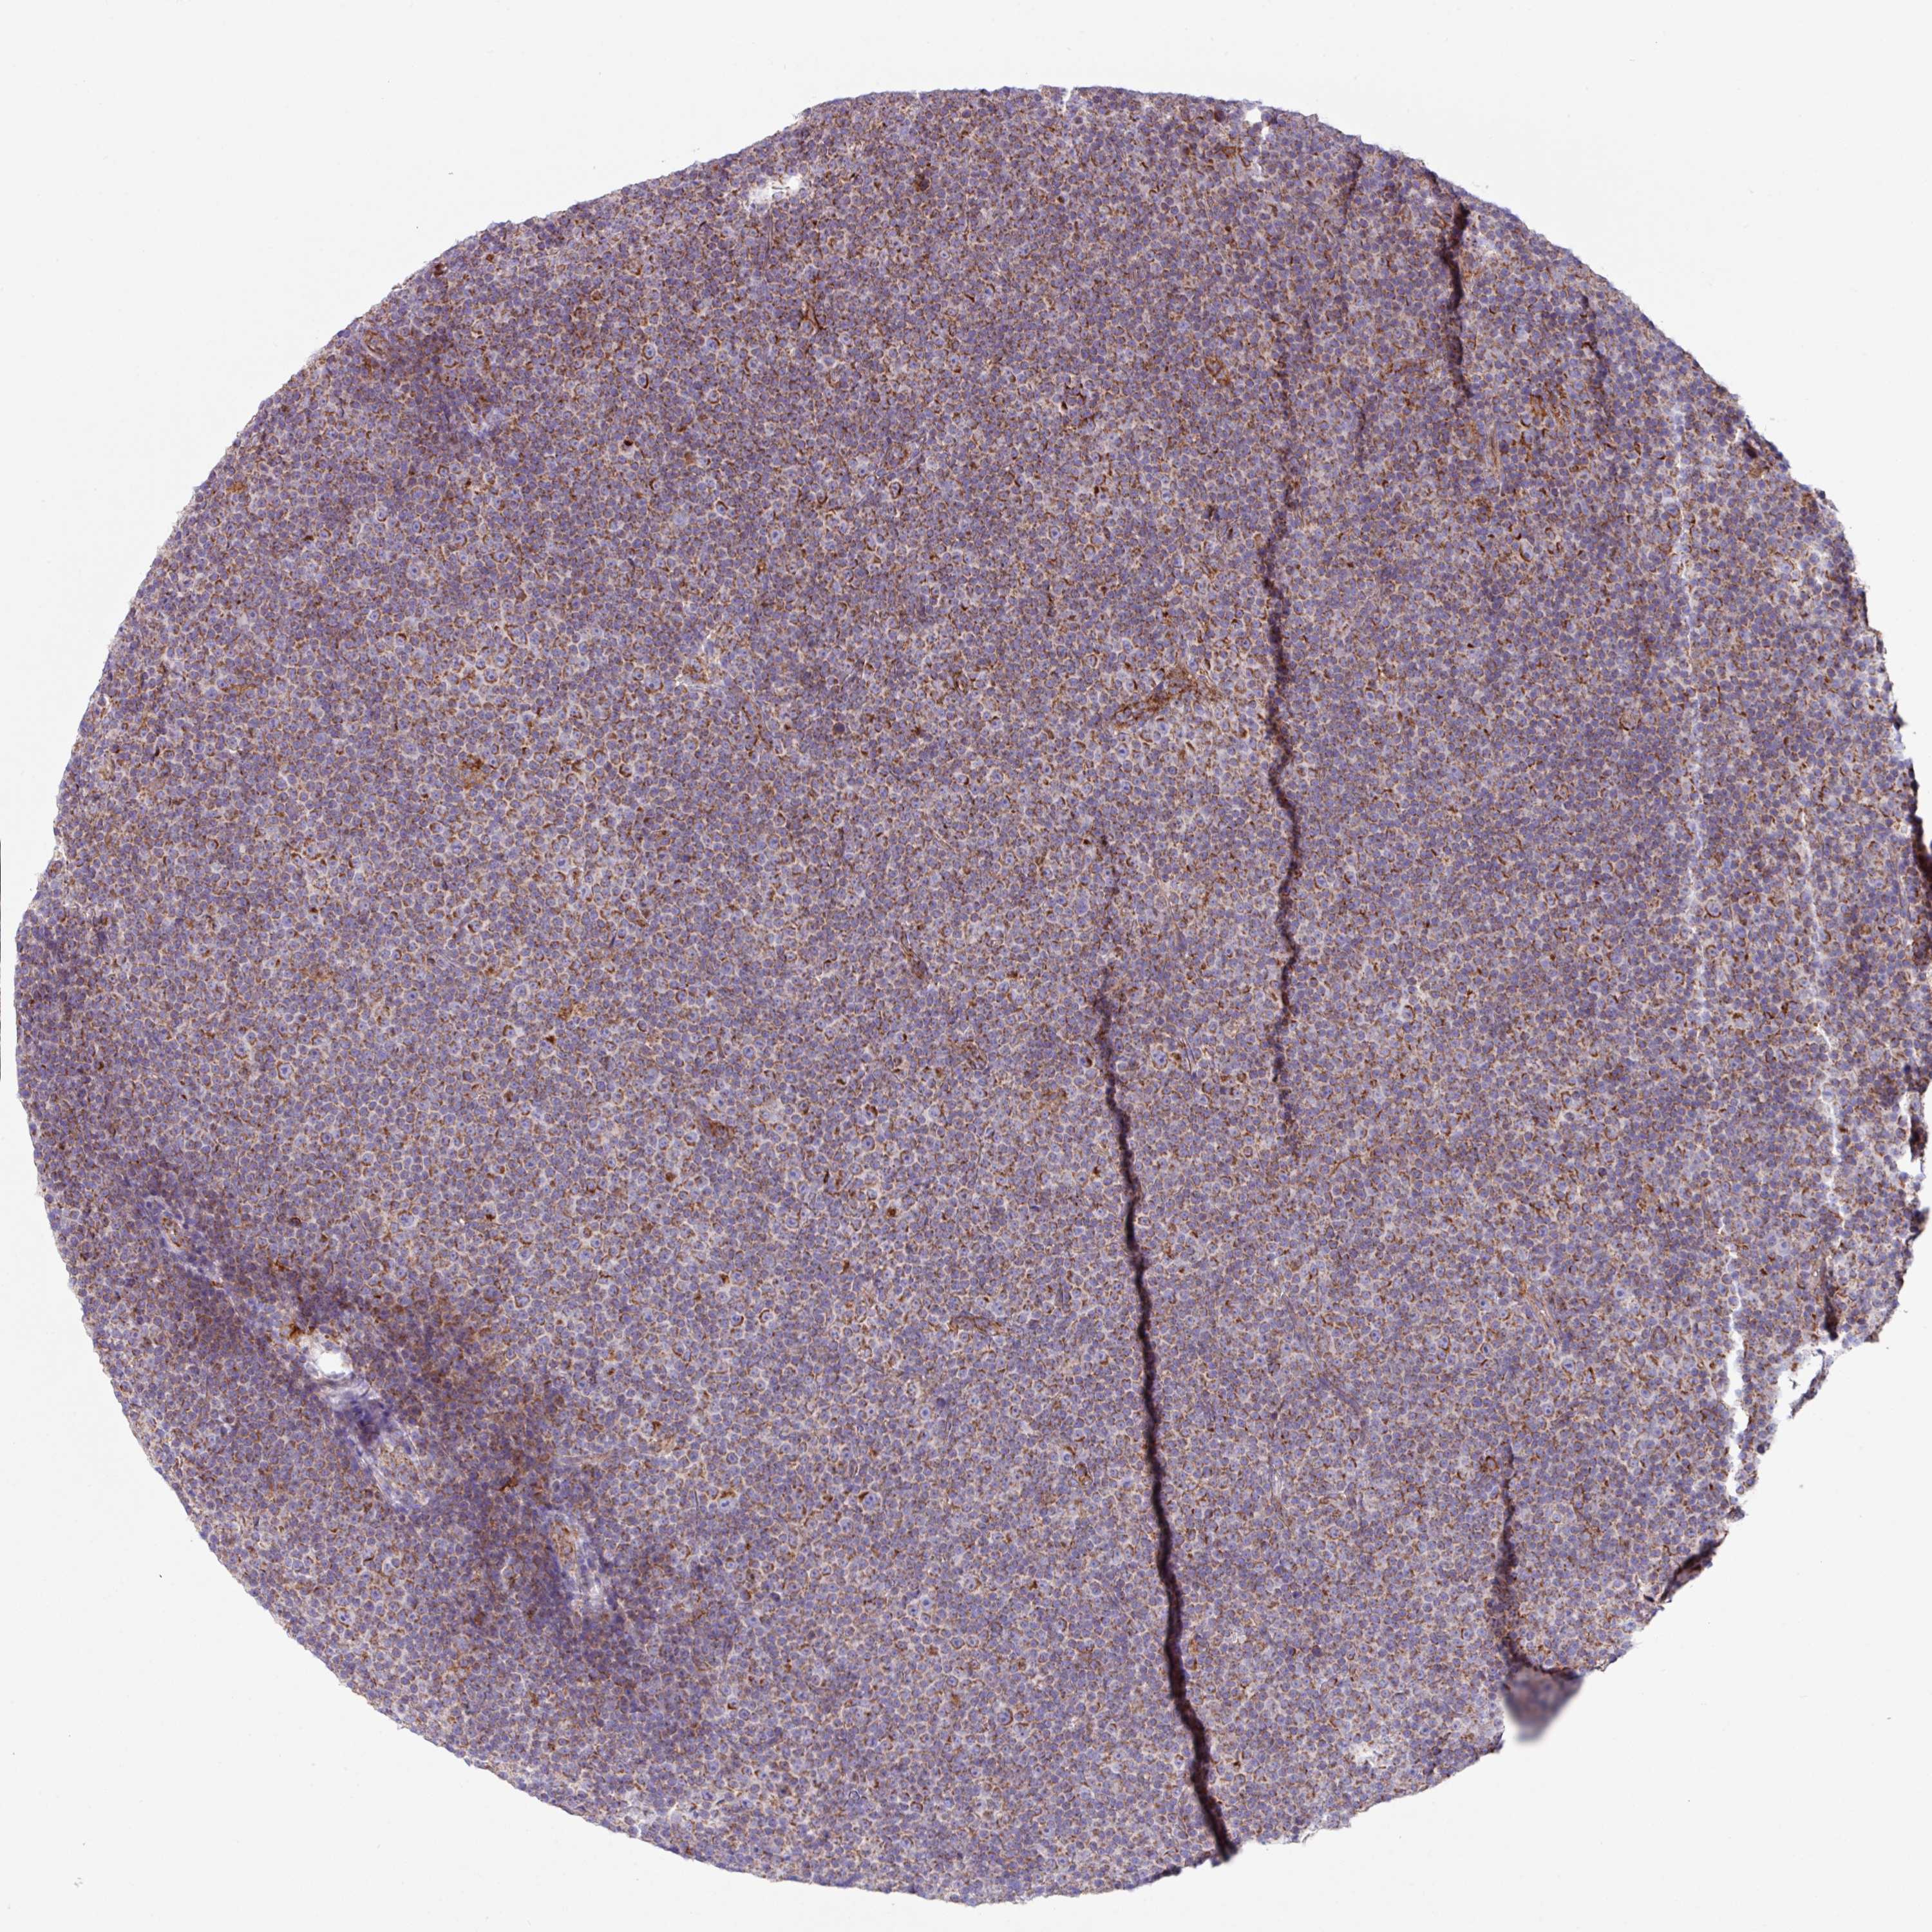

LYMPHOMA - Protein expressioni

A mouse-over function shows sample information and annotation data. Click on an image to view it in a full screen mode. Samples can be filtered based on level of antibody staining by selecting one or several of the following categories: high, medium, low and not detected. The assay and annotation is described here.

Antibody stainingi

Antibody staining in the annotated cell types in the current human tissue is reported as not detected, low, medium, or high, based on conventional immunohistochemistry profiling in selected tissues. This score is based on the combination of the staining intensity and fraction of stained cells.

Each image is clickable and will lead to virtual microscopy that enables deeper exploration of all samples and also displays staining intensity scores, fraction scores and subcellular localization as well as patient and tissue information for each sample.

Antibody HPA051074

Staining

High

Medium

Low

Not detected

Intensity

Strong

Moderate

Weak

Negative

Quantity

>75%

75%-25%

<25%

None

Location

Nuclear

Cytoplasmic/membranous

Cytoplasmic/membranous,nuclear

Malignant lymphoma, non-Hodgkin's type, Low grade